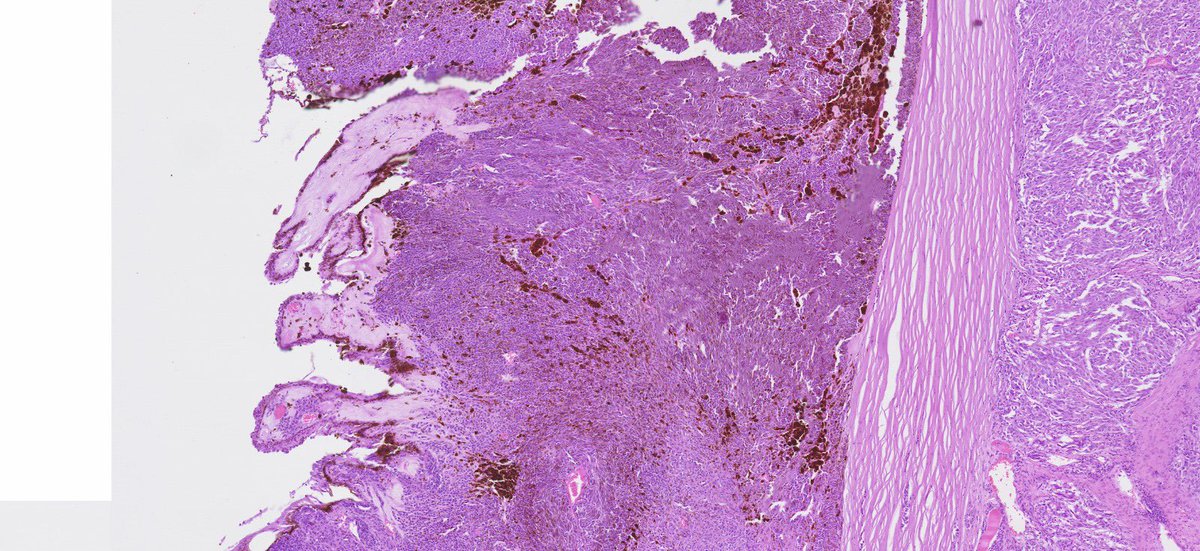

The frozen section